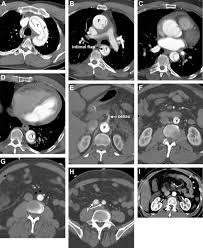

how muchhow ishow 42how kilogramshow inhow poundshow exhibit966sswdftrs_finalhow 2010how ACCFAHAAATSACRASASCASCAISIRSTSSVMhow Guidelineshow forhow thehow how Diagnosishow andhow Managementhow ofhow Patients